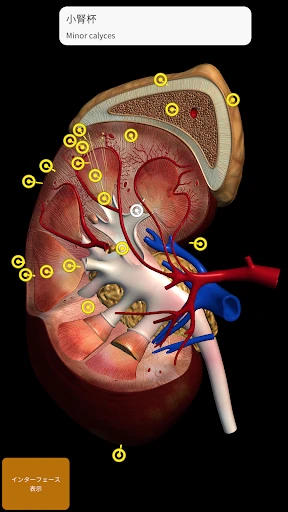

皆さん、3Dで人体を探検したことはありますか?このアプリを使うと、まるで本物の標本を手に取っているかのように、人体の構造を詳細に観察できます。何よりも嬉しいのは、非常にリアルなグラフィックスです。3Dモデルはとても精密で、筋肉や骨、内臓の位置関係が一目瞭然です。

この「解剖学 - 3Dアトラス」、ただのビジュアルツールにとどまりません。かなり多くの情報が詰まっています。例えば、各部位の詳細な説明や、医学用語の解説も充実しているので、学習にはもってこいです。特に、試験勉強中の学生さんには非常に役立つことでしょう。

私のお気に入りの機能の一つは、特定の部位を選択すると、その部位に関する詳細な情報が表示されることです。これにより、単なるビジュアルだけでなく、知識を深めることができるのです。